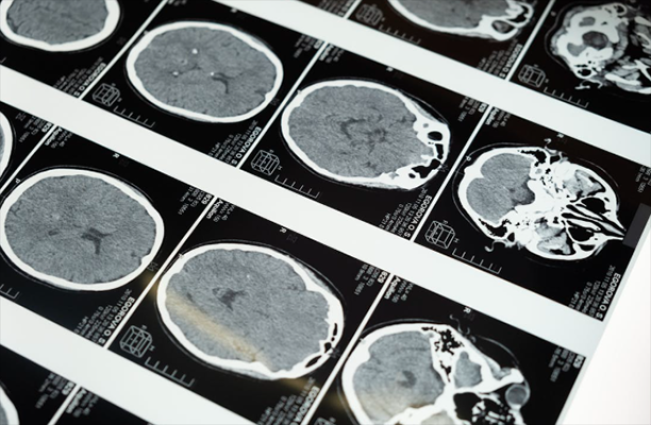

Tumor dapat diidentifikasi dengan CT scan atau MRI, dan diagnosis dikonfirmasi dengan biopsi jaringan. “Beberapa faktor memengaruhi lamanya seseorang dapat hidup dengan glioblastoma,” kata Georges, “termasuk kesehatan mereka secara keseluruhan, fungsi neurologis saat diagnosis, usia, dan seberapa baik mereka merespons pengobatan seperti pembedahan, radiasi, dan kemoterapi.”